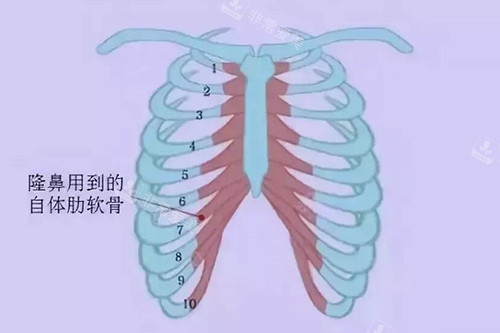

肋骨隆鼻:900万韩元。

这是朴院长的头牌项目之一。

价格反映了技术的复杂性和材料的优越性(自体肋软骨量足、支撑力强)。

特别适合鼻基础较差、需要强力支撑。

或者追求非常立体、持久结果的求美者。